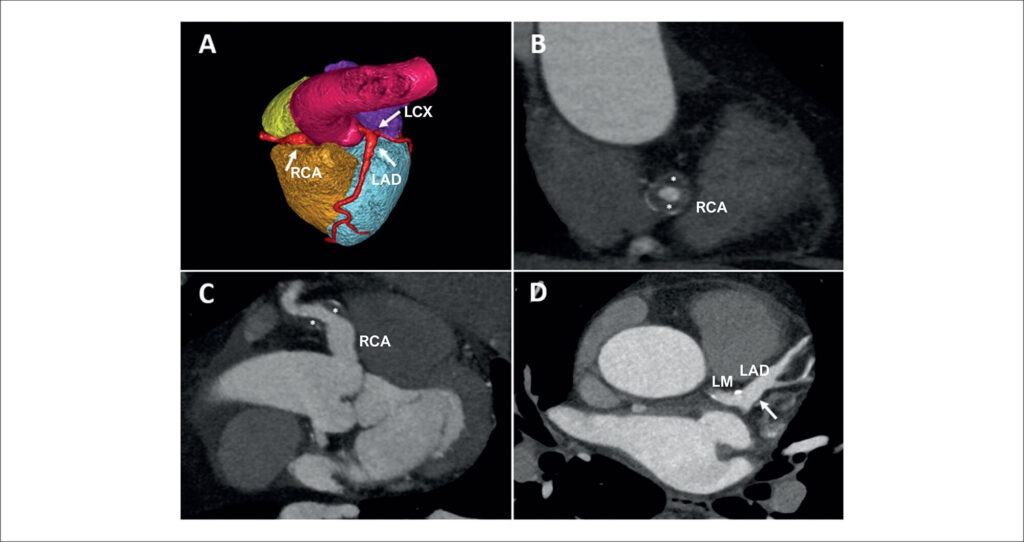

A 54-year-old patient with no previous medical history was evaluated in the cardiology clinic for chest pain with atypical characteristics. Due to a pretest probability of ischemic heart disease of 20%, a coronary computed tomography scan was performed, which showed a coronary aneurysm (10 × 11 mm) from the origin of the right coronary artery (RCA) to the mid-segment (, white arrow; ). In the RCA mid-segment, there was partial circumferential thrombosis with 50% lumen stenosis ( and ; , white asterisks). The rest of the RCA showed no coronary artery obstruction. A 9 × 9 mm aneurysm was also observed in the left main coronary artery extending to the bifurcation and proximal portion of the left anterior descending coronary artery, without significant lesions ( and , white arrows; ). A 5 × 6 mm aneurysm was also observed in the proximal left circumflex artery, without significant coronary lesions (, white arrow; ). The study was completed with a regadenoson stress cardiac magnetic resonance that was negative for inducible ischemia. Serologies and autoantibodies were also requested, and they were negative. The decision was made to initiate medical treatment with acetylsalicylic acid and atorvastatin. During the 6-month follow-up, the patient did not present coronary outcomes and remained asymptomatic.